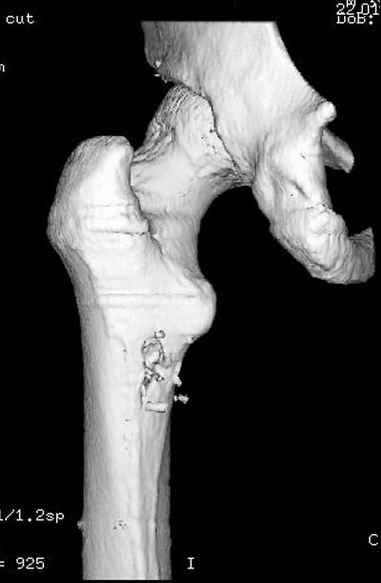

Больной с огнестрельным переломом бедра с вовлечением около 15% медиального кортекса, входное отверстие около 1 см в диаметре; стабильный, без сосудистых и неврологических признаков.

Учитывая, что больной получил травму не во время визита в церковь, и он является одним из представителем 40 миллионного “outstanding itizen”, без медицинской страховки, без работы в свои 39 лет, и без надлежающей ортопедической дисциплины у которого отсутсвует страх стрессового перелома, было рекомендовано оперативное лечение: профилактическое антеградное интрамедуллярное штифтование.

Методика штифтования при отсутствии большой зоны перелома как при онкологических профилактических штифтованиях, расверливание интрамедуллярного канала проводим с предварительным наложением дополнительного дренажного отверстия в дистальном отделе бедра (в данном случаи в канале оставили 6.5 мм канюлированный шуруп), иначе при создании давления в канале во время сверления имеется опасность эмболизации легочной артерии тромбом.